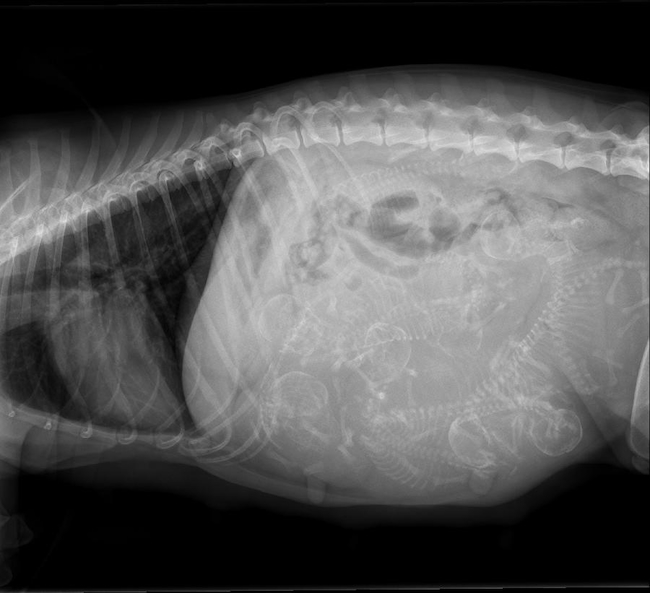

Bobbie bevallen op woensdag 15 oktober Een paar dagen eerder dan uitgerekend is Bobbie bevallen van 7 prachtige pups. Er zijn 2 abrikoos teefjes, 2

Een paar dagen eerder dan uitgerekend is Bobbie bevallen van 7 prachtige pups. Er zijn 2 abrikoos teefjes, 2 bruine reutjes en 3 zwarte reutjes.

Bobbie doet het fantastisch en is heerlijk relaxed. De bruine reutjes en een zwart reutje zijn flink aan de maat. Alle pups groeien goed. Op dit moment valt er verder nog niet veel te vertellen en is het eigenlijk alleen maar een kwestie van drinken en slapen.